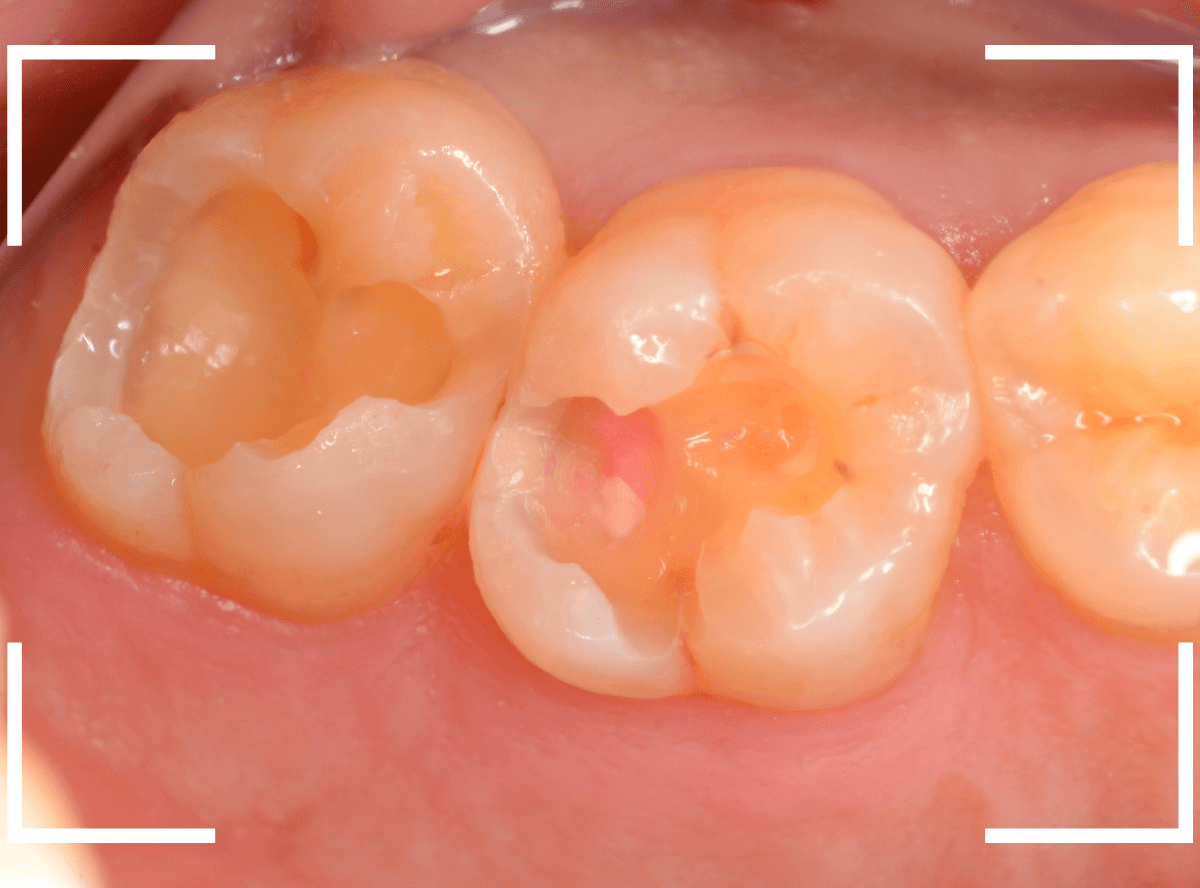

Case.9 隣の歯まで虫歯が進行していたケース

上の奥歯が痛むという訴えで来院された患者さんです。

一番奥の歯(左)が虫歯になっているのが一目でわかります。

虫歯も深そうです。

レントゲン写真で確認します。

赤い線が虫歯、青い線が歯の神経です。

歯の神経までは少し距離がありそうですが、深い虫歯であるのはわかります。

となりのつめもの(レジン)の下も虫歯になっているのがわかります。

治療を開始します。

赤く染まっている部分が虫歯です。

思った通り、かなり深く進行していますね。

奥歯の虫歯が全部除去できましたので、手前の歯の虫歯も治療します。

全ての虫歯を除去しました。

レントゲンから予測した通り、かなり広範な虫歯でした。

お薬をつめて、しばらく症状がないか経過観察後、つめものを作る治療に移ります。